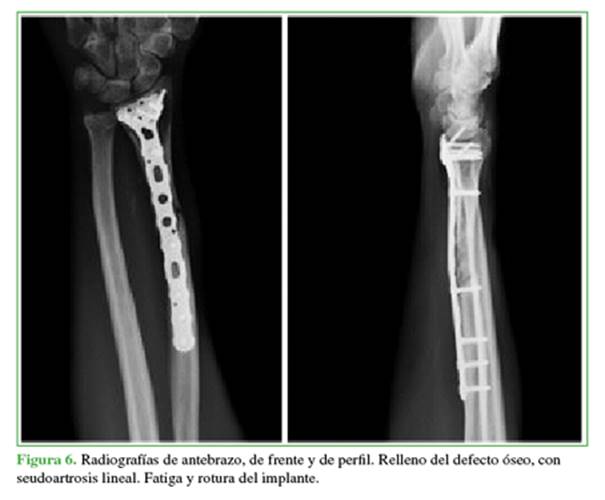

Nuevamente refirió dolor durante la carga a los ocho meses de la cirugía. En las radiografías, se observó el relleno del defecto óseo, pero con persistencia del foco de seudoartrosis lineal y fallo del implante por fatiga (Figura 6).